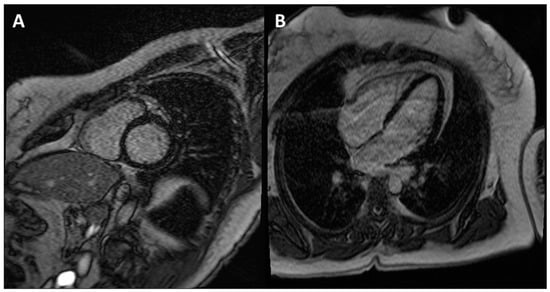

Figure 5.

CE-CMR images in patients with ACM without RV morpho-functional abnormalities and LGE. (A) Short axis two-chamber view. (B) Long axis four-chamber view. (C) RV electroanatomic mapping depicting an epicardial scar on the RV free wall. Unipolar voltage map showing low voltages consistent with an epicardial scar. (D) Bipolar voltage map showing normal voltages.